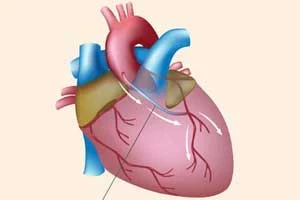

CABG (Coronary Artery Bypass Grafting)

Advanced bypass surgery to restore blood flow to heart

Open Heart Surgery

Comprehensive surgical procedures for complex heart conditions

CABG (Coronary Artery Bypass Grafting)

Advanced bypass surgery to restore blood flow to heart

Open Heart Surgery

Comprehensive surgical procedures for complex heart conditions